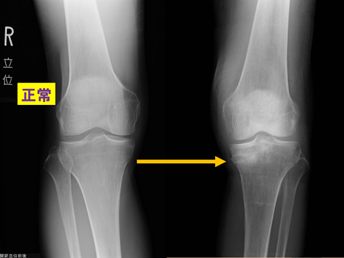

①変形性ひざ関節症などは有名ですが(下図)

②関節リウマチ(下図)

③半月板損傷(下図)